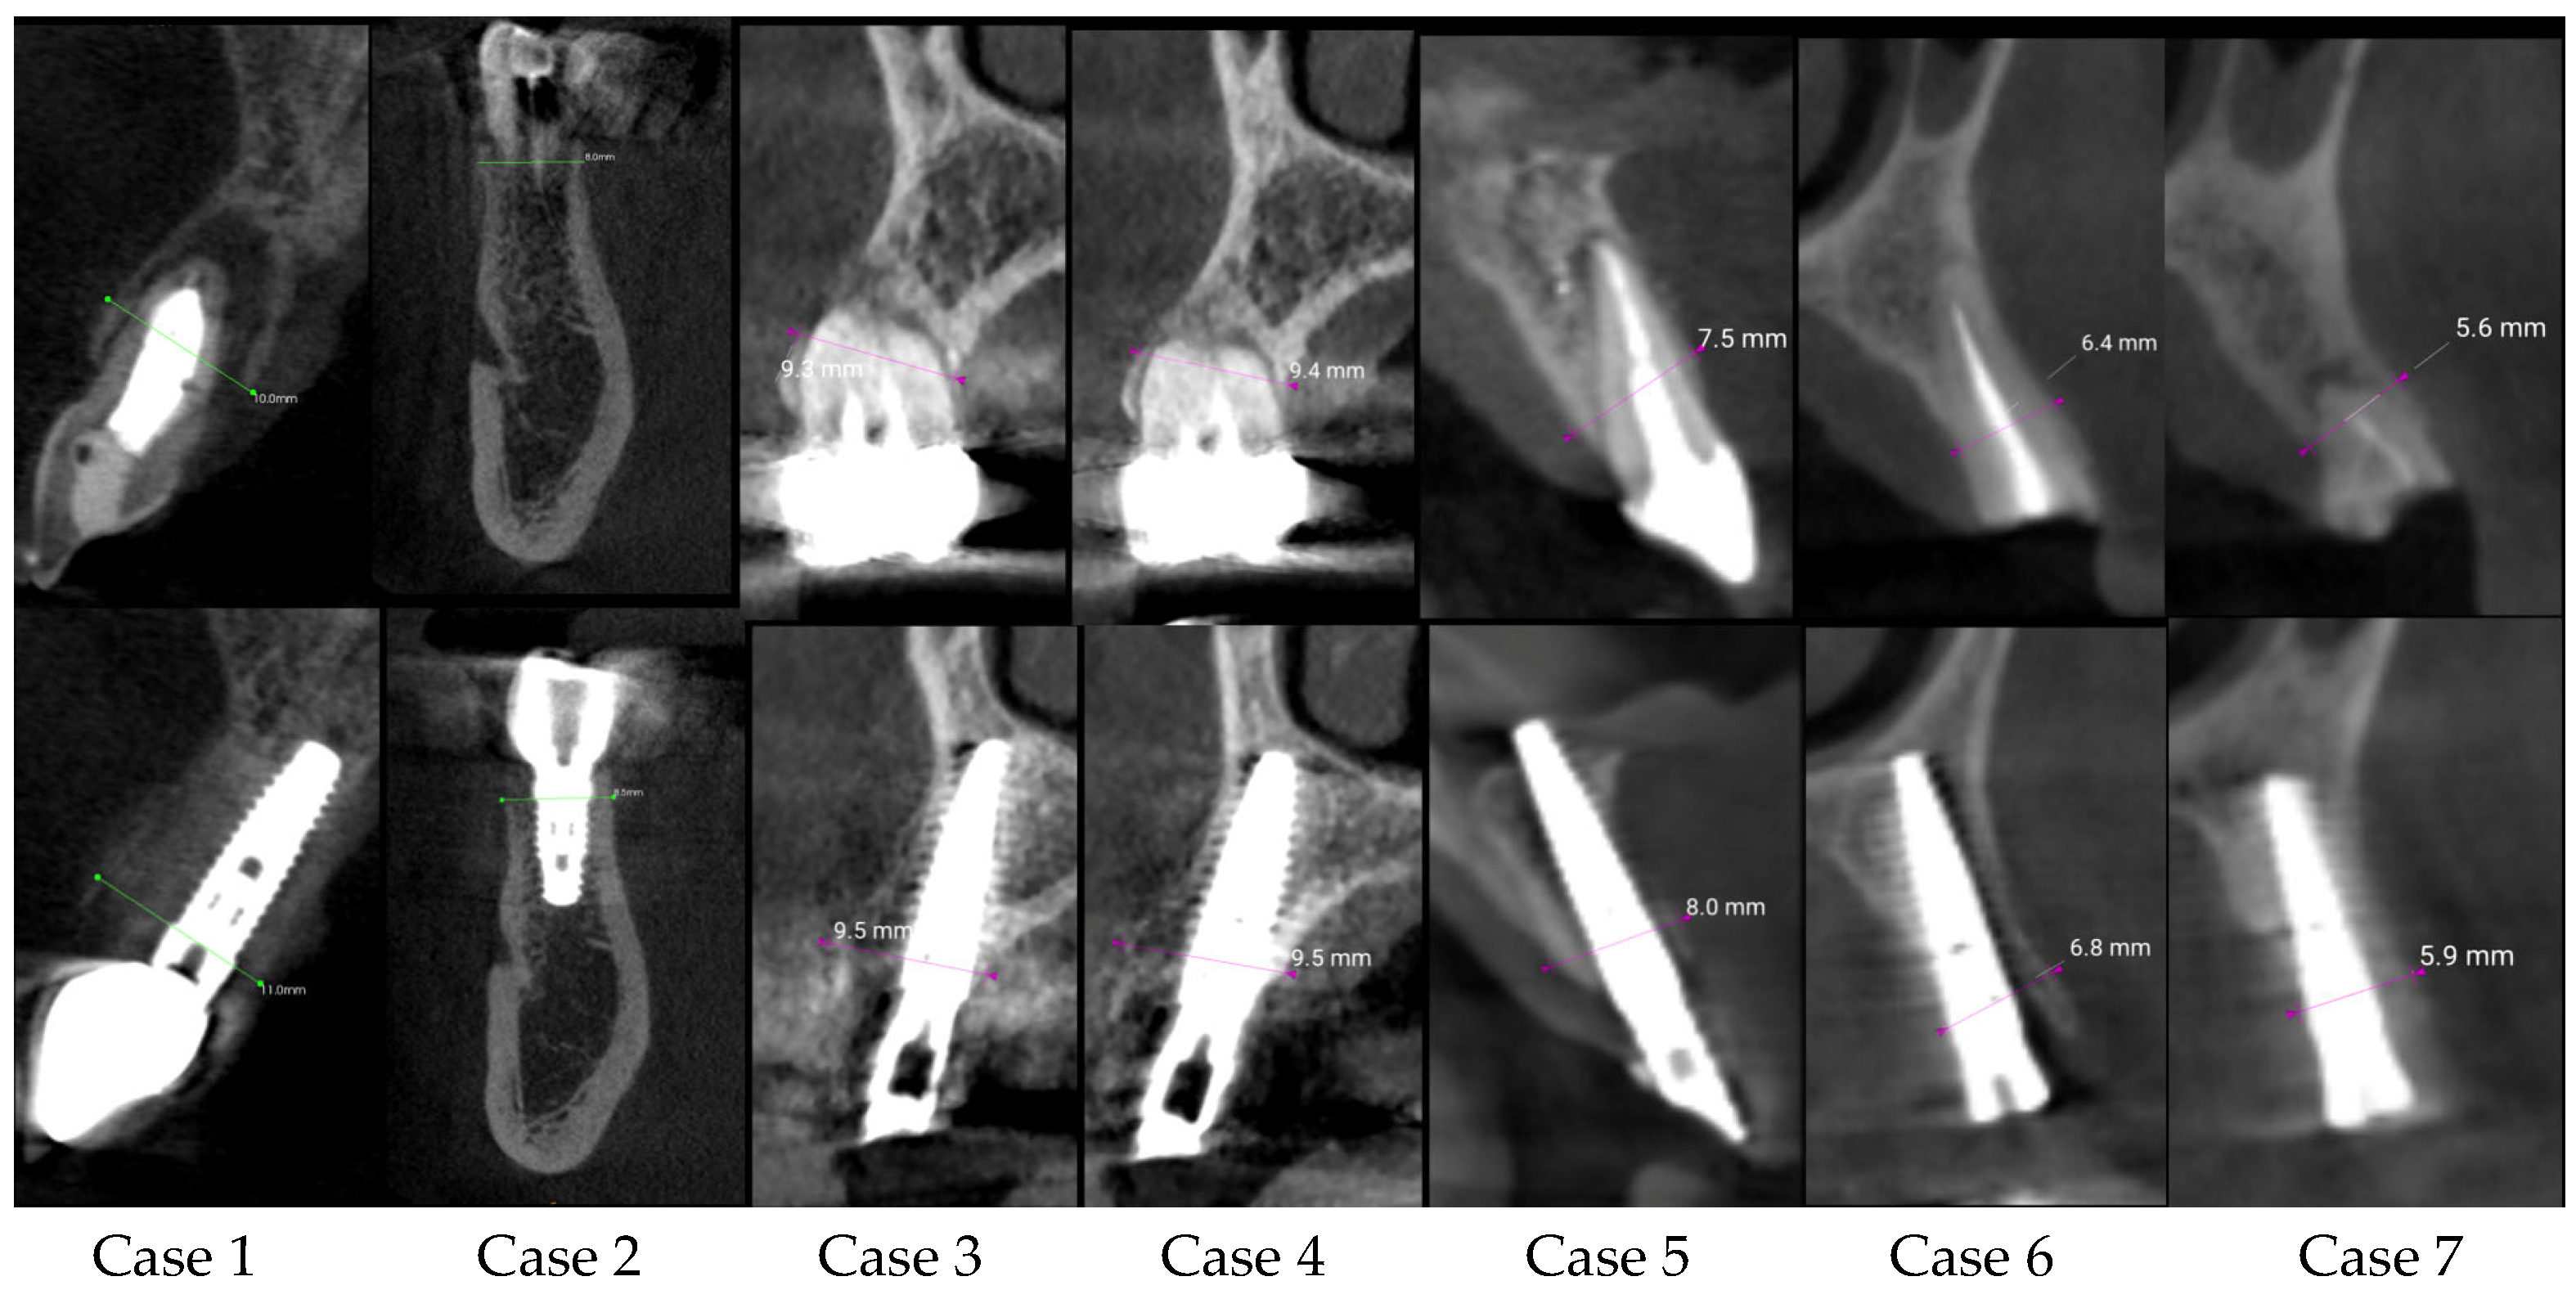

| Center/Case | Sex/Age | Tooth Number | Ridge Thickness before (mm) | Ridge Thickness after (mm) | Follow-Up Time | Difference | Immediate Loading |

|---|---|---|---|---|---|---|---|

| C1 case 1 | Female/31 | 21 | 10.00 | 11.00 | 6 months | 1.00 | yes |

| C1 case 2 | Male/63 | 45 | 8.00 | 8.50 | 12 months | 0.50 | no |

| C2 case 3 | Female/50 | 15 | 9.00 | 9.50 | 6 months | 0.50 | yes |

| C2 case 4 | Female/50 | 14 | 9.40 | 9.50 | 6 months | 0.10 | yes |

| C2 case 5 | Female/71 | 21 | 7.50 | 8.00 | 6 months | 0.50 | yes |

| C2 case 6 | Female/63 | 23 | 6.40 | 6.80 | 6 months | 0.40 | yes |

| C2 case 7 | Female/63 | 24 | 5.60 | 5.90 | 6 months | 0.30 | no |

| C2 case 8 | Male/68 | 42 | 6.40 | 6.90 | 6 months | 0.50 | yes |

| C3 case 9 | Male/62 | 21 | 7.18 | 7.20 | 8 months | 0.02 | yes |

| C3 case 10 | Male/58 | 17 | 10.52 | 11.69 | 5 months | 1.17 | yes |

| C1 case 11 | Male/68 | 24 | 10.10 | 10.70 | 6 months | 0.60 | yes |

| C3 case 12 | Female/46 | 11 | 7.81 | 8.43 | 7 months | 0.62 | yes |

| C2 case 13 | Male/77 | 24 | 12.00 | 12.70 | 6 months | 0.70 | yes |

| C1 case 14 | Male/74 | 13 | 7.9 | 8.1 | 4 months | 0.20 | no |

| Before | After | p-Value | ||

|---|---|---|---|---|

| Ridge thickness (mm) | 14 | 8.4 ± 1.8 | 9.0 ± 2.0 | p < 0.0001 |